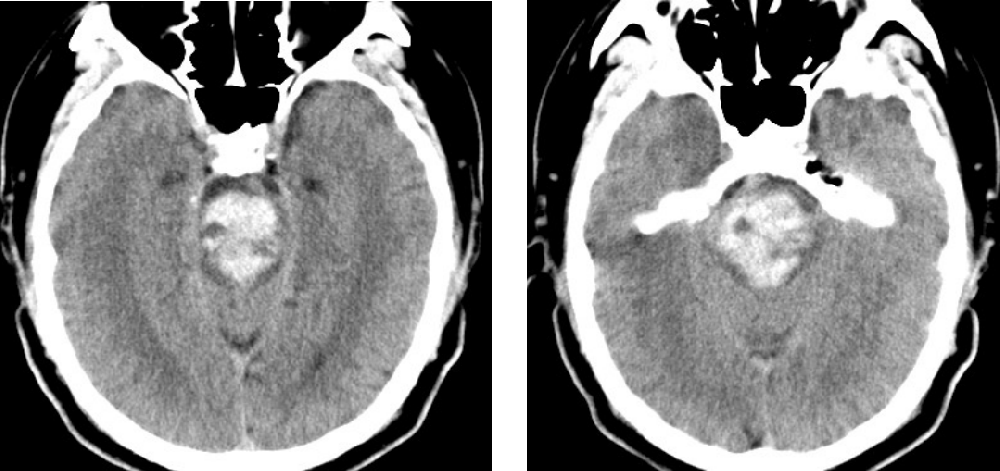

患者,男,45歲,1月2日因“突發(fā)昏迷1小時”被同事送至我院,急診CT檢查示腦干大量出血,出血量約15ml。此時患者已深度昏迷,各項生理反射消失,自主呼吸不穩(wěn)定,肢體強直并出現(xiàn)中樞性高熱,體溫40℃。因病情危重、隨時可能出現(xiàn)呼吸心跳驟停,緊急收入重癥監(jiān)護室,給予氣管插管、呼吸機通氣,維持各項生命指標(biāo)治療。

附手術(shù)前患者顱腦CT: